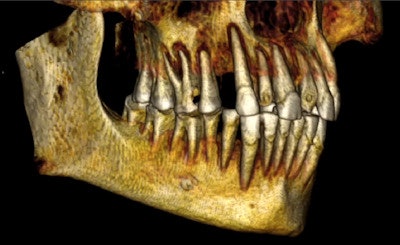

The whole-body CT scans were performed at the Montreal Neurological Institute and Hospital using an Aquilion One 320-slice scanner (Toshiba America Medical Systems) with 0.5-mm-thick slices, offering much greater detail than the CT imaging performed in 1995 and also the ability to create 3D reconstructions, using Vital Images' Vitrea software and OsiriX software.

Curved planar reformatted CT image. Note the carious lesions on the left first and second molars. Image courtesy of Andrew D. Wade, PhD.

Overall, the dental condition of the mummy is poor, the researchers reported. The maxillary and mandibular teeth show occlusal attrition and abrasion, while the maxillary teeth also have numerous periapical abscesses and large interproximal carious lesions.

"Abscesses were found at the apices of the maxillary right first molar and second incisor and of the left first incisor and molars," they wrote. "The abscesses of the left maxillary molars communicate with the maxillary sinus and inferior meatus. Interproximal caries are noted in the maxillary right second premolar."

The researchers also identified the mass previously found by Dr. Langsjoen in the carious lesions of the left first and second molars, and described it as a low-density, homogeneous ball of material, such as linen. It measures 7.7 x 7.1 x 3.7 mm, larger than the lesion's opening of 5.5 x 6.8 mm, but it remains loose within the cavity, they noted.

3D reconstruction shows the worn incisors. Image courtesy of Andrew D. Wade, PhD.